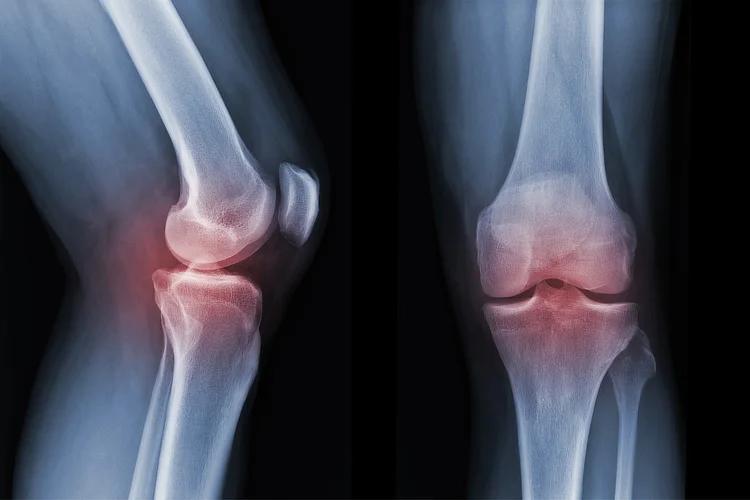

X-ray showing damaged knee joint due to arthritis, often requiring total knee replacement.

• Medical Evaluation – Blood tests and X-rays, with an MRI if needed, to assess your fitness for the procedure and identify potential risks.